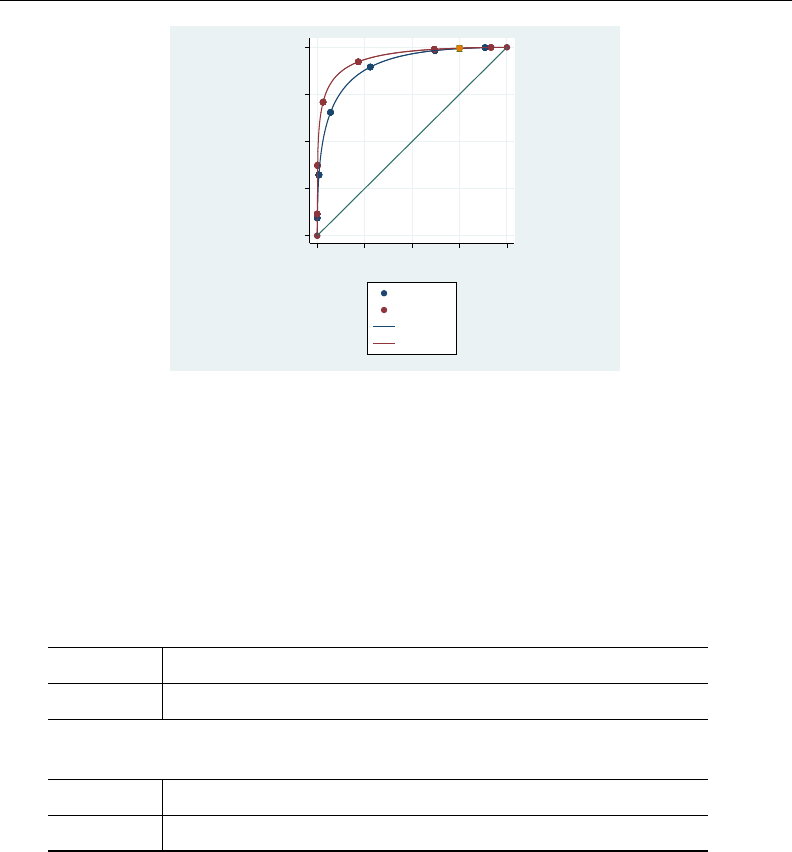

- roc

- roccomp

- rocfit

- rocfit postestimation

- rocreg

- rocreg postestimation

- rocregplot

- roctab